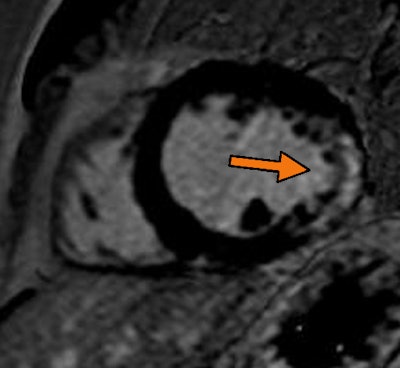

| Midchamber short-axis view from late gadolinium enhancement on cardiac MRI. Arrow shows transmural scar with an ischemic pattern at the later wall. Image from the Clinical Hospital of Ribeirão Preto in Brazil, courtesy of Dr. Gustavo Volpe. |